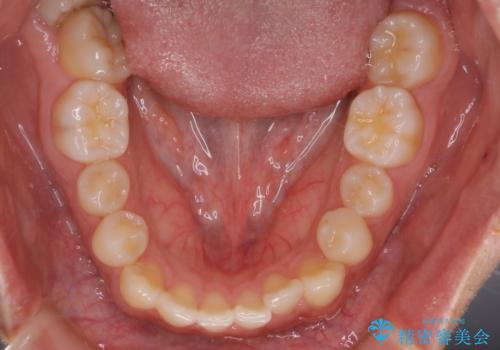

- 前歯のがたつきを主訴に来院されました。初診時、右上2番の口蓋側転位と右下7番の舌側傾斜が認められました。

インビザラインにてIPRと歯列弓拡大を行い、ゴム掛けで噛み合わせを改善する治療計画を立てました。

マウスピースの使用時間が短いため、シュミレーション通り進むか不安でしたが

治療期間1年で、主訴である前歯のがたつきを改善出来、

奥歯の噛み合わせも良くなりました。